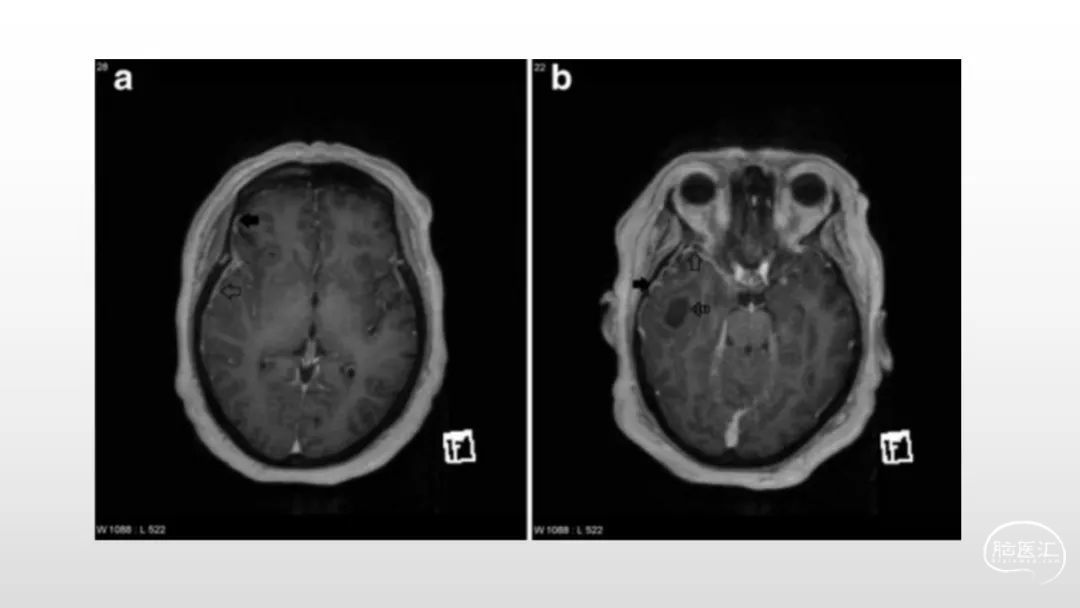

颅脑影像诊断基础知识讲座:脑膜病变